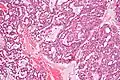

Microscopically, its histology can be confused with an adenoid cystic carcinoma and a pleomorphic adenoma.

Polymorphous low-grade adenocarcinoma. H&E stain.

Micrograph of a polymorphous low-grade adenocarcinoma. H&E stain.

PLGAs consist of a monomorphous cell population that has a varied histologic morphology.